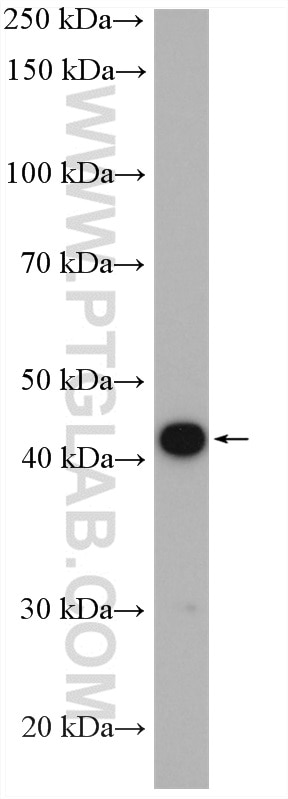

| Positive WB detected in | rat kidney tissue |

| Calculated Molecular Weight | 383 aa, 42 kDa |

| Observed Molecular Weight | 42 kDa |

NPHS2 (also known as Podocin) is a membrane protein located on the podocyte foot process and is the critical component of the glomerular filtration barrier. Mutations of NPHS2 cause recessive steroidresistant nephrotic syndrome. Two isoforms of NPHS2 exist with molecular weights of 42 kDa and 35 kDa, respectively. (PMID: 21499232)